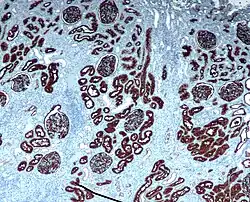

CD10 is used in clinical pathology for diagnostic purpose.

In lymphomas and leukemias

- Acute lymphoblastic leukemia (ALL) cells are CD10+.

- Follicular lymphoma (follicle centre cell lymphoma) are CD10+.

- Burkitt Lymphoma cells are CD10+.

- CD10+ diffuse large B cell lymphoma (CD10+ DLBCL)[20]

- Angioimmunoblastic T cell lymphoma (AITL) are CD10+[25][26] and distinguishes AITL from other T cell lymphomas (CD10−)[27]

- Some benign T cells can be CD10+[28]

In epithelial tumors

- Clear cell renal cell carcinoma (Clear cell RCC)

- CD10+ distinguishes renal cell carcinoma, conventional type with eosinophilic morphology from its mimickers. Chromophobe carcinoma and oncocytoma are CD10−.[29]